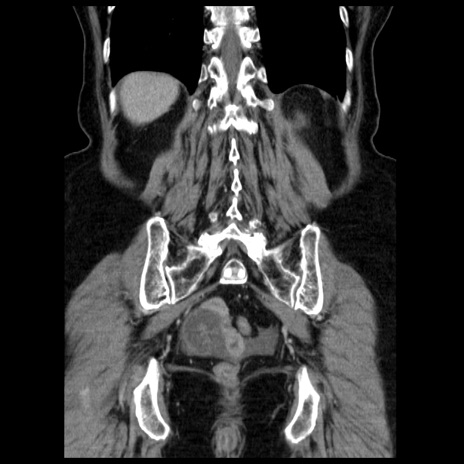

症例13(冠状断像)

【症例】70歳代女性

【主訴】腹痛、嘔吐

【現病歴】15時間程前(昨晩)より腹痛あり。今朝になっても症状の改善なく、嘔吐あり。腹痛も増悪あり、救急外来受診。

【既往歴】子宮癌全摘術後

【身体所見】意識清明、BP 121/72mmHg、P 74bpm、SpO2 100%(RA)、腹部:平坦・軟、腸雑音ほぼ聴取せず。下腹部・心窩部・臍左上に圧痛あり。反跳痛なし。

【データ】WBC 10600、CRP 0.15